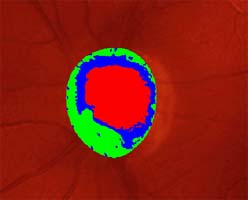

Očekávali byste protažení exkavace k hornímu pólu terče, jak nám ukazuje tento snímek z tomografu HRT II.

exkavace levé oko

Na kterém oku je exkavace větší, na pravém nebo na levém? Podle pohledu na fotografie jistě na levém.

exkavace pravé oko

Co je příčinou toho, že při pohledu na snímky hodnotíme rozsah exkavace nesprávně? Je to skutečnost, že i růžová oblast neuroretinálního lemu může být již prohloubená, což vídáme zvláště na počátku rozvoje glaukomové neuropathie.